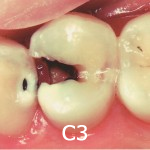

C3(歯髄に達するむし歯)- 虫歯が歯の中心にある神経(歯髄)に達し、神経が炎症を起こした状態です。神経が圧迫され激しい痛みに襲われます。麻酔をして歯を大きく、深く削り神経を除去します。